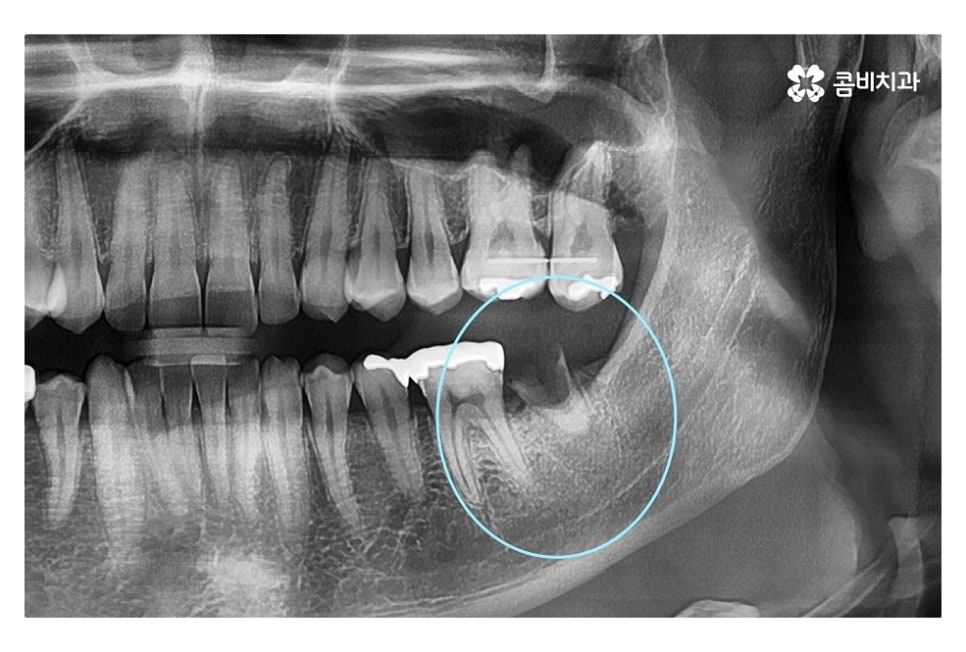

같은 환자분의 사진인데 좌측 치아의 경우 신경치료 후 크라운으로

마무리를 했지만 우측 어금니의 경우 치아의 대부분이

손상이 되어 결국 발치 후 임플란트를 하게 된 사례라고 할 수 있는데요.